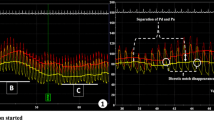

Figure 3a provides a visual depiction and representative example of simultaneous coronary and LV hemodynamic measurements following intra-arterial ISDN administration as a function of time; a simultaneous drop in LV pressure and subtle increase in coronary blood flow velocity can be seen at 15–20 s. Figure 3b demonstrates the same hemodynamic measurements averaged over one cardiac cycle with coronary wave energies at baseline and following ISDN.

Simultaneous coronary and LV data acquisition. a Representative example of simultaneous coronary and LV hemodynamic measurements following intra-arterial ISDN administration as a function of time. From top to bottom, the panels display continuous intra-cardiac ECG recording, left ventricular pressure (LVP), left ventricular volume (LVV), distal coronary pressure (Pd), and mean coronary flow velocity (U). b demonstrates simultaneous coronary and LV hemodynamic measurements at baseline and following intra-arterial ISDN administration averaged over one cardiac cycle with coronary wave energies at baseline and following ISDN. c demonstrates simultaneous coronary and LV hemodynamic measurements at baseline and during exercise averaged over one cardiac cycle and coronary wave energies at baseline and during dynamic exercise

Left ventricular hemodynamic measurements at baseline and following ISDN are presented in Table 2. Graphical representation of LV and coronary hemodynamic measurements are presented in Fig. 2a–g. Administration of intra-arterial ISDN resulted in a leftward, downward shift of the pressure-volume loop compared to baseline (Fig. 2i). Administration of intra-arterial ISDN resulted in a reduction in left ventricular pressures (end-diastolic pressure 8.3±6.4 versus 13.1±6.2mmHg, P<0.001; end-systolic pressure 96.0±19.0 versus 122.7±18.0mmHg, P<0.001) and left ventricular volumes (end-diastolic volume 102.7±129.5 versus 112.1±32.7mL, P=0.01, end-systolic volume 36.1±15.6 versus 44.3±15.3mL, P=0.04) compared to baseline. On administration of intra-arterial ISDN, there was a reduction in afterload (arterial elastance 1.3±0.5 versus 1.6±0.5 mmHg/mL, P=0.003) and a reduction in stroke work (6348±2670 versus 7243±2637mmHg.mL, P=0.002) and pressure-volume area (1.15±0.4 versus 1.49±0.56J, P<0.001) compared to baseline. Administration of intra-arterial ISDN resulted in increased LV mechanical efficiency as a ratio of stroke work to pressure-volume area (73.8±9.0 versus 65.2±6.3%, P=0.001). There was also an improvement in the active diastolic properties of the ventricle (Tau 32.5±4.3 versus 34.1±4.6ms; P=0.038) but a decrease in magnitude of load-dependent markers of diastolic function (dP/dTmin −906±355 versus −1284±179mmHg/s; P=0.011).

Graphical demonstration of changes induced by ISDN and exercise. a–g Heart rate, ST segment, power output, EDP, EDP dPdtmax, and coronary flow velocity changes from baseline following administration of ISDN or dynamic exercise. Measurements are at baseline, 50% peak, and peak effect. H LV pressure-volume relations at baseline (black solid line), 50% peak (broken line), and peak exercise (solid red line). Peak exercise effect is associated with increased myocardial demand, stroke volume, and LV pressures. i LV pressure-volume relations at baseline (black solid line), 50% peak (broken line), and peak ISDN effect (solid red line). Peak ISDN effect is consistent with a decrease in stroke work, increase in LV efficiency, and reduction in myocardial oxygen consumption